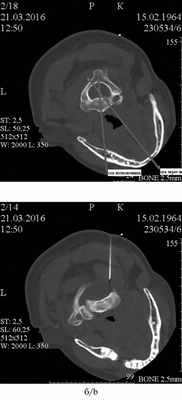

Также КТ-исследование является важным в диагностике тортикапута, когда необходима оценка аксиальных срезов на уровне II и VI шейного позвонков (рис. 3, а), и для выявления гипертрофированной нижней косой мышцы шеи. При характерных признаках тортикапута и определении гипертрофированной нижней косой мышцы шеи целесообразно сразу ввести в нее БТА (см. рис. 3, б).

Рис. 3. КТ-исследование.

а — смещение оси, проведенной через тело VI шейного позвонка, относительно оси, проведенной через нижнюю челюсть; б — положение иглы при введении БТА в гипертрофированную нижнюю косую мышцу головы.